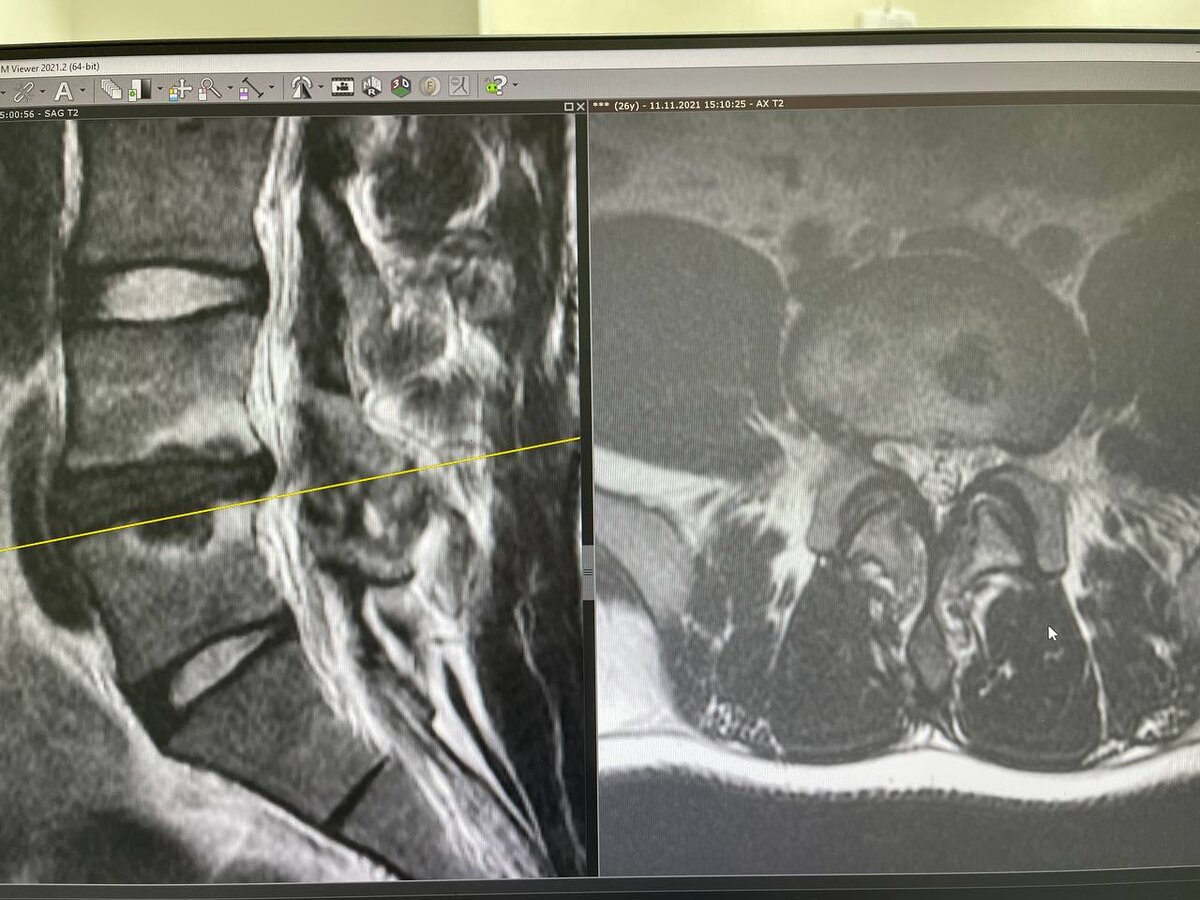

Грыжа Шморля - это «выпячивание» хрящевой ткани межпозвонковых дисков, но не внутрь позвоночного канала, как это бывает при обычной грыже, а внутрь тела верхнего или нижнего позвонка.

Впервые эта морфологическое образование было описано немецким патологом, Кристианом Шморлем в 1927 году. По предположениям, оно связано с высокой осевой нагрузкой, особенно в грудном и поясничном отделе позвоночнике.

Диагностика грыж Шморля не вызывает затруднений так, как их видно даже на стандартных рентгеновских снимках.